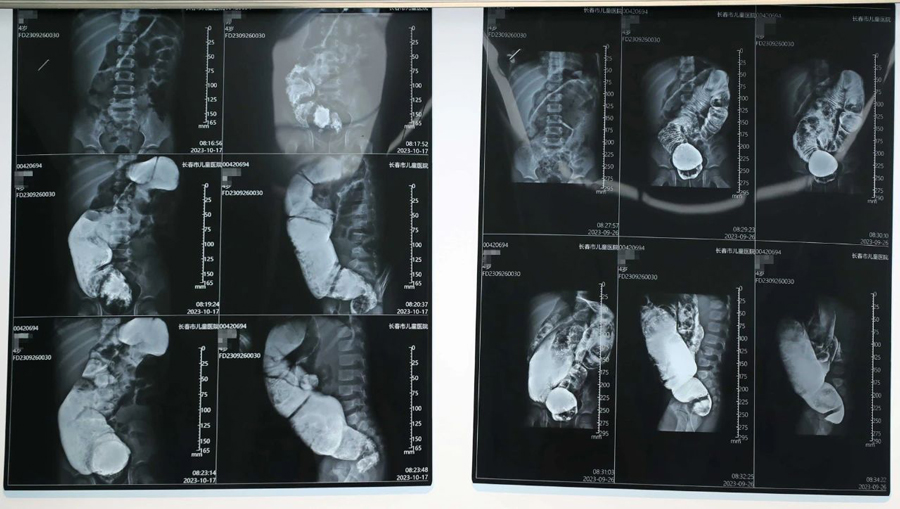

小旭本应在出生后3—6个月手术最佳,但因种种原因,治疗被拖延了。检查中医生发现,小旭为短段型巨结肠,因病程太长,导致肠管梗阻扩张严重、病情复杂,其中,扩张肠管最宽处可达12cm。手术切除缺乏神经节细胞的狭窄肠段及扩张失去正常功能的扩张段肠管,这是目前最有效的治疗方法。医生经过与家长反复沟通,确定了手术治疗方案。

经过充分的术前准备,小旭的肠道具备了手术条件,在完成相关检查和化验后,10月21日,首都医科大学附属北京儿童医院移植科主任、普通外科副主任、医学博士张廷冲,携手德州扑克游戏网 普外、新生儿外科主任崔钊团队,以及麻醉科、手术室人员,共同组成手术团队,行腹腔镜辅助下巨结肠根治术。张廷冲博士主刀,团队默契配合,先游离盆腔病变肠管,这一操作要求精细、精确解剖,难度很大,一旦损伤输尿管、盆神经和盆底肌肉,容易日后出现大小便失禁。术中取快速病理,使手术切除病变肠管更为精准、可靠。接下来,打开肛门黏膜层,拖出切除肠管,将保留的正常肠管与肛管黏膜吻合。在团队的共同努力下,手术的一系列操作都非常顺利,切除病变肠管约45cm,实现了精准、微创、安全、美观。